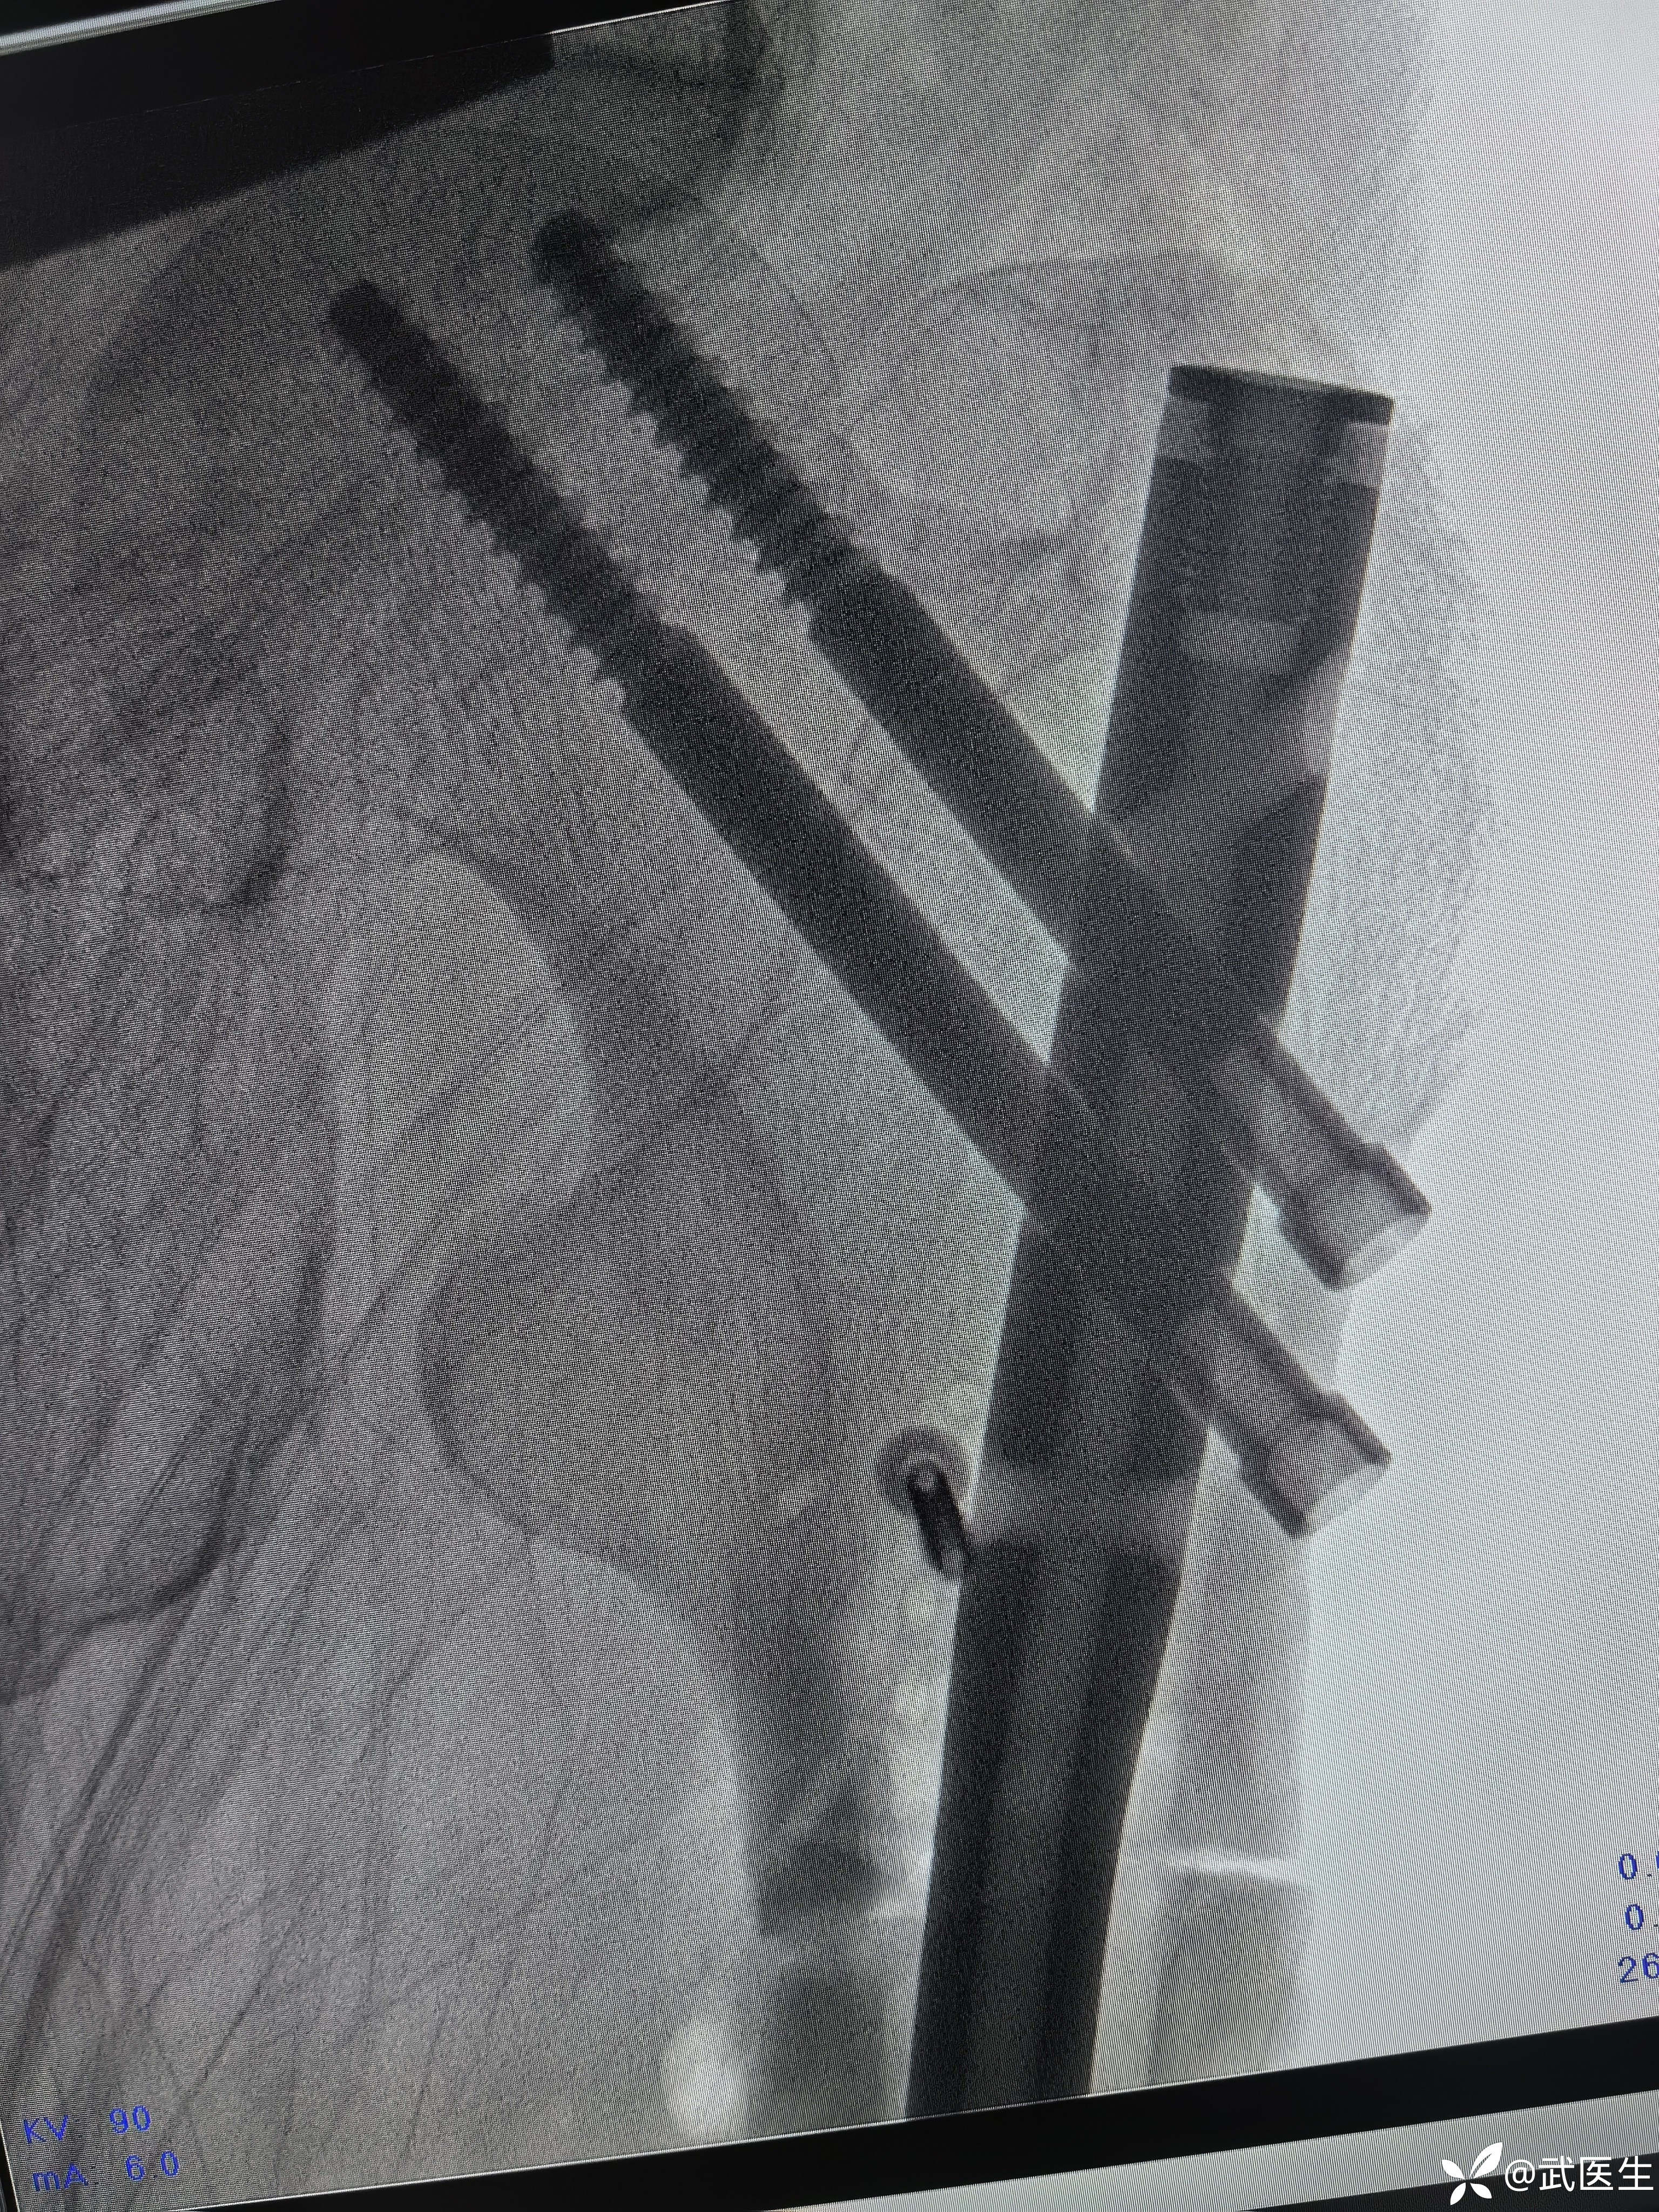

断端向外成角,对位不好,经常出现的问题,退出髓内钉,打阻挡克氏针,

置入

成角纠正,断端间隙有点大

捶足底,纵向挤压

间隙缩小

侧位前方出现蝶形骨块

阻挡克氏针更换为阻挡钉